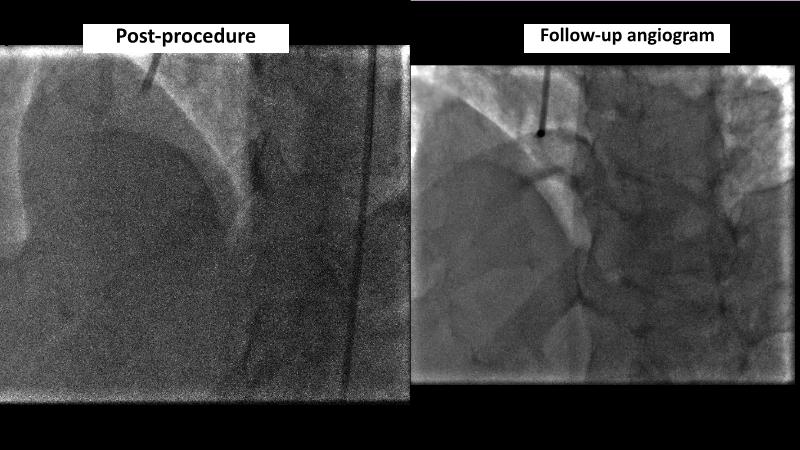

Browse this EuroPCR 2024 session to explore the safety and efficacy of sirolimus-coated balloons from pre-clinical data, review MagicTouch data from real-world populations with case-based examples, and learn about the MagicTouch sirolimus-coated balloon clinical programs. Discover insights and takeaways from the significance of the EASTBOURNE subgroups, and analyze the challenges and opportunities in PCI for diabetic patients.

- To learn from the real world registries and complex cases to understand the practical implications and potential of the device in diverse patient population